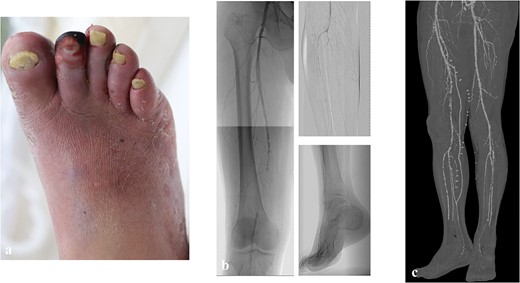

A 60-year-old man with diabetes mellitus and end-stage renal failure following 10-year maintenance hemodialysis was hospitalized for infected gangrene of the second digit. He had a history of percutaneous coronary intervention for ischemic heart disease. According to preoperative evaluation, his WIfI stage was 4 (wound grade 2, ischemia grade 3, foot infection grade 2), and the GLASS stage was II (target artery path: posterior tibial artery, femoropopliteal grade 2, infrapopliteal grade 2) (Fig. 1a and b) as assessed using the Global Vascular Guidelines [1]. Revascularization (superficial femoral artery-posterior tibial artery bypass with great saphenous vein) and open amputation of the second digit were performed (Fig. 1c).

The preoperative clinical picture of case 1; (a) gangrene of the second digit with infection; (b) preoperative angiography; the GLASS stage was II (TAP: posterior tibial artery, FP2, IP2); (c) postoperative computed tomography; superficial femoral artery-posterior tibial artery bypass with a great saphenous vein was performed.